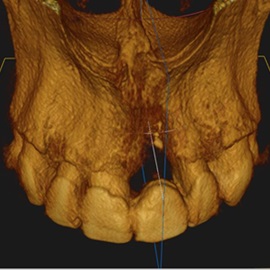

Pacjentka lat 72, od kilkudziesięciu lat chorująca na cukrzyce I typu, obecnie od 10 lat na pompie insulinowej. Profesor medycyny, siostrzenica pacjentki prowadzi swoją ciocię diabetologicznie, pacjentka świadoma zagrożeń przy zabiegach regeneracji kości i implantacji w takim ogólnym stanie zdrowia. Po rekonstrukcji tkanek miękkich i kości osadzono dwa implanty o średnicy 5,0 mm. Na zdjęciu śródzabiegowym widać zadowalające wyniki rekonstrukcji tkanki kostnej. Po upływie kilku miesięcy wykonano nadbudowę protetyczną.